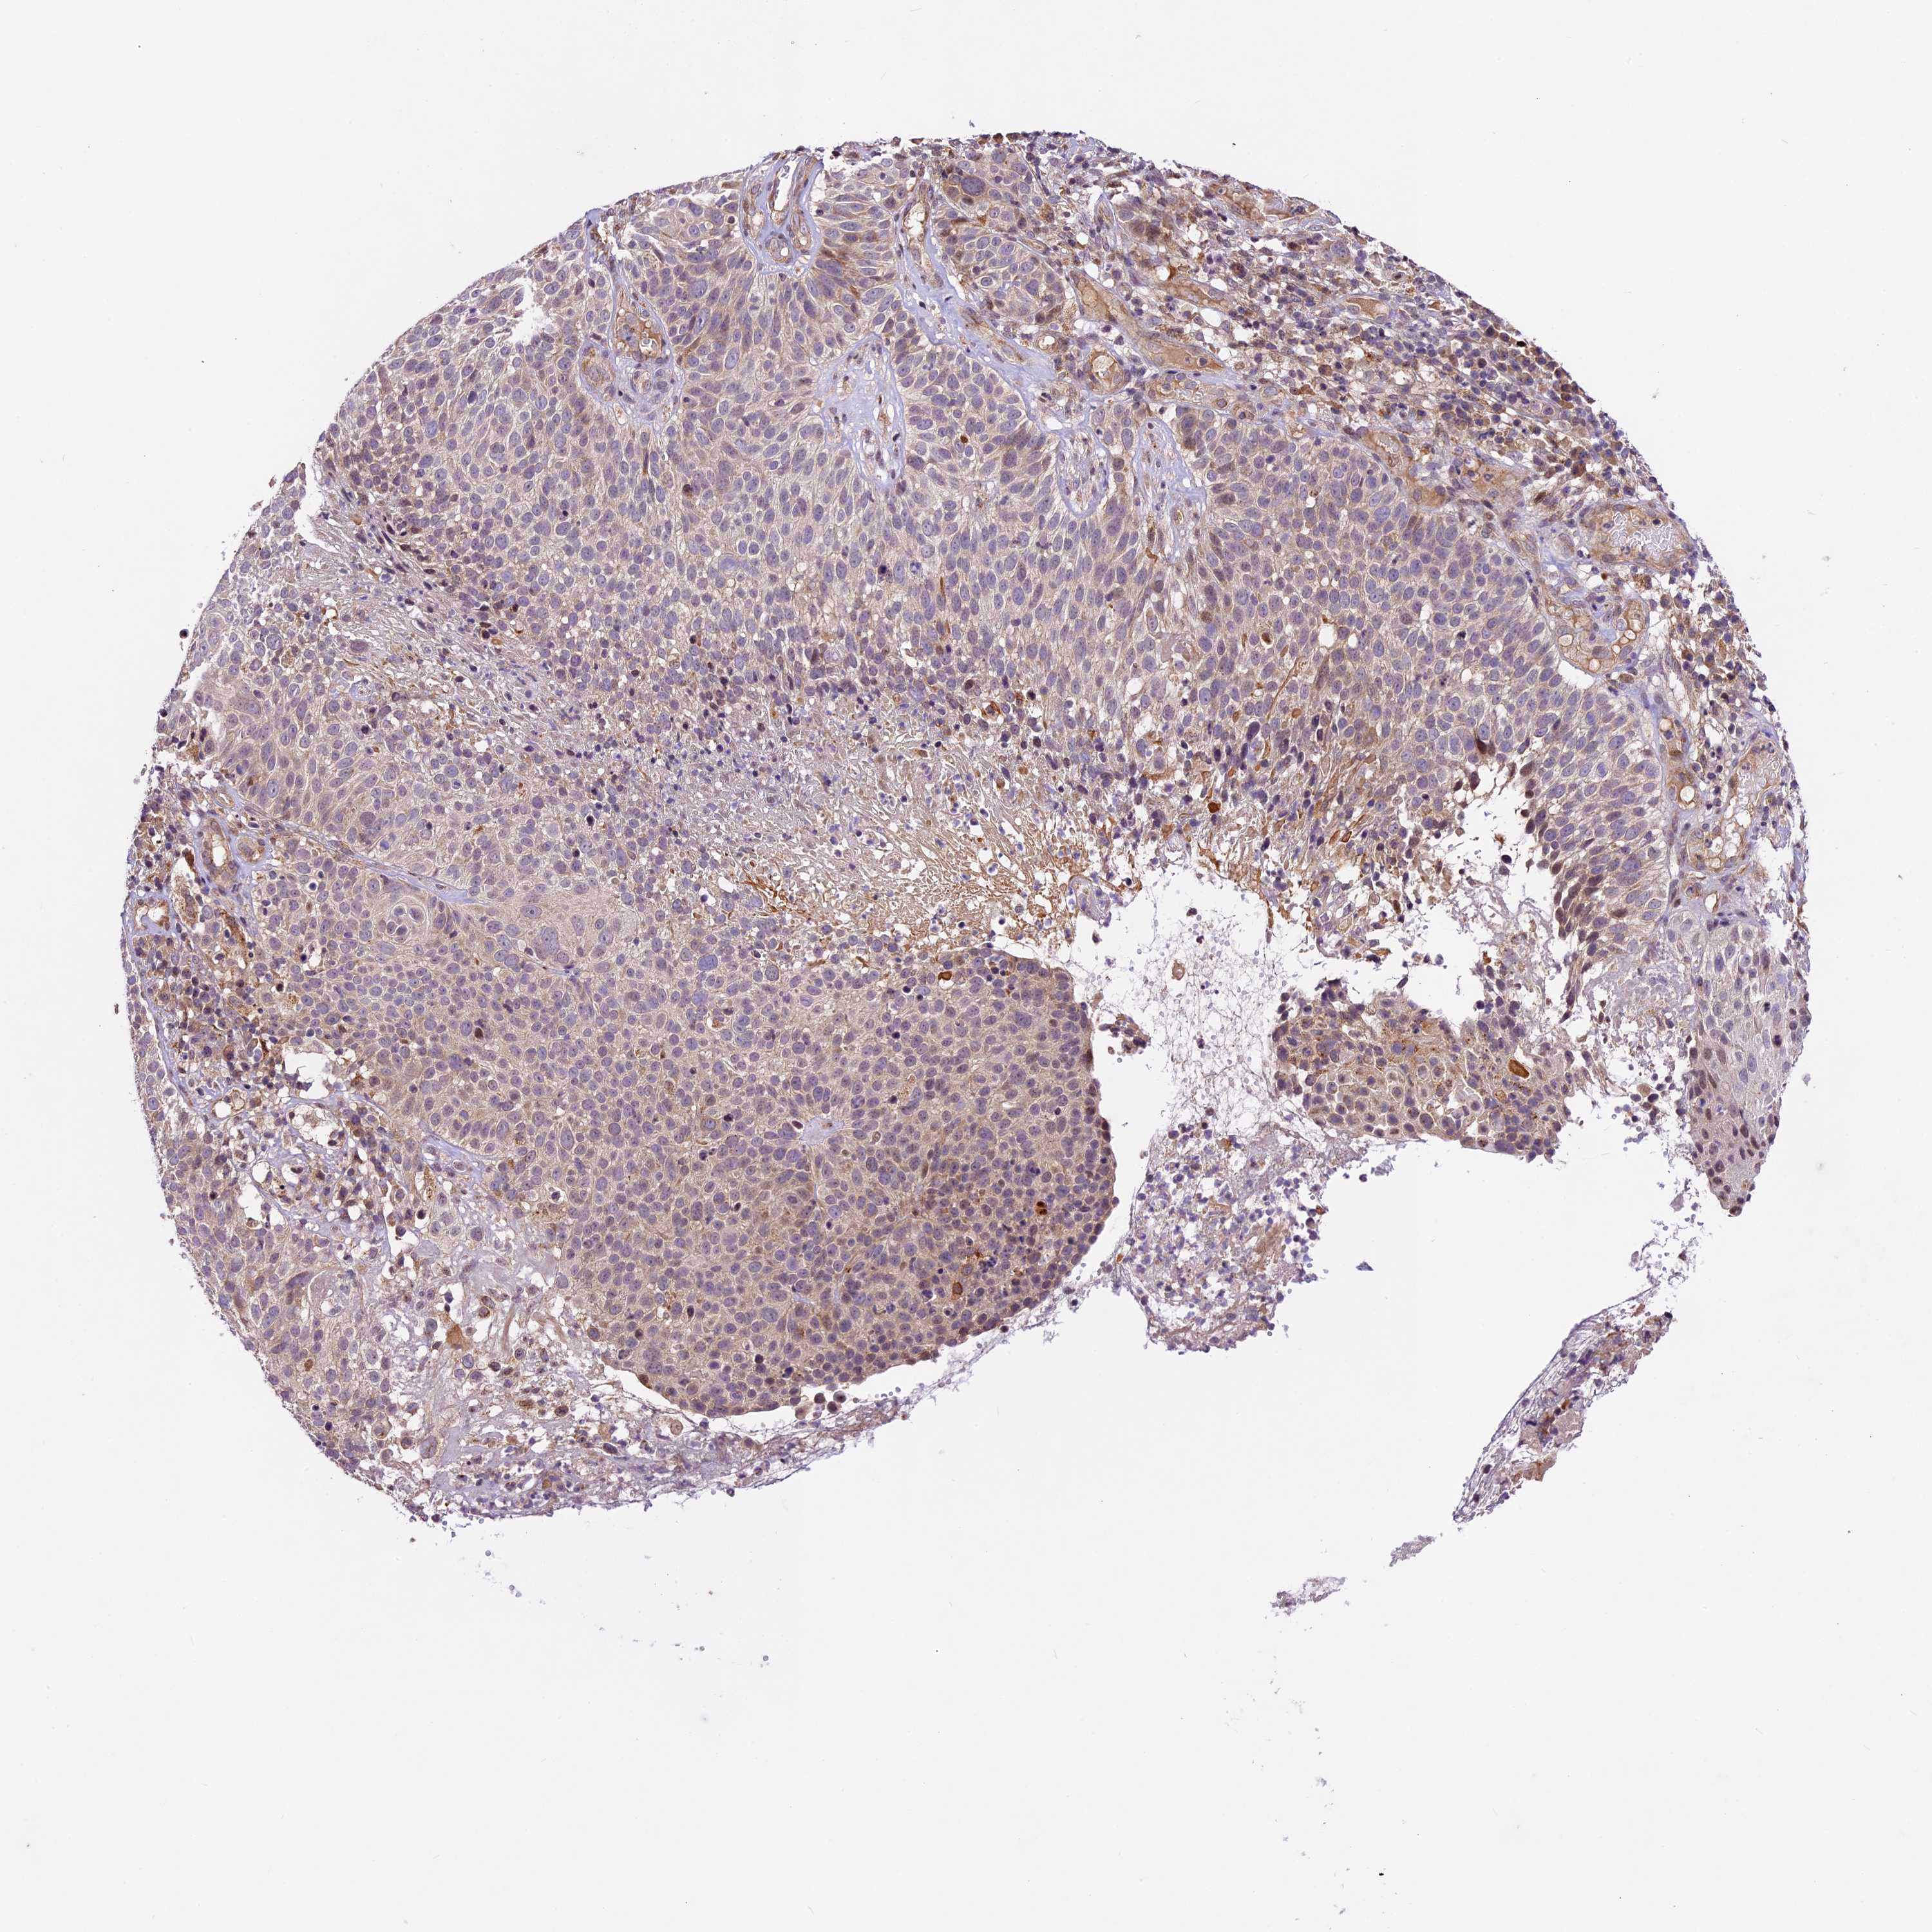

CERVICAL CANCER - Protein expressioni

A mouse-over function shows sample information and annotation data. Click on an image to view it in a full screen mode. Samples can be filtered based on level of antibody staining by selecting one or several of the following categories: high, medium, low and not detected. The assay and annotation is described here.

Note that samples used for immunohistochemistry by the Human Protein Atlas do not correspond to samples in the TCGA dataset.

Antibody stainingi

Antibody staining in the annotated cell types in the current human tissue is reported as not detected, low, medium, or high, based on conventional immunohistochemistry profiling in selected tissues. This score is based on the combination of the staining intensity and fraction of stained cells.

Each image is clickable and will lead to virtual microscopy that enables deeper exploration of all samples and also displays staining intensity scores, fraction scores and subcellular localization as well as patient and tissue information for each sample.

Antibody HPA041880

Antibody HPA054709

Squamous cell carcinoma, NOS

Adenocarcinoma, NOS